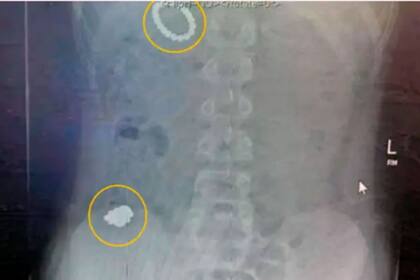

Cuando su mamá lo llevó al hospital, los médicos le hicieron una radiografía y se sorprendieron al encontrar 54 pequeños juguetes magnéticos en su estómago e intestino. Como los especialistas temían que las bolitas imantadas pudieran dañar órganos vitales, Rhiley debió ser intervenido de urgencia, en una cirugía donde se le extrajeron los objetos. La operación duró seis horas.

“Me quedé atónita, sin palabras cuando escuché el número que se había tragado. Los médicos adivinaron alrededor de 25-30 bolitas en la radiografía, pero después de la cirugía dijeron que tenía 54”, relató la mamá, de 30 años.